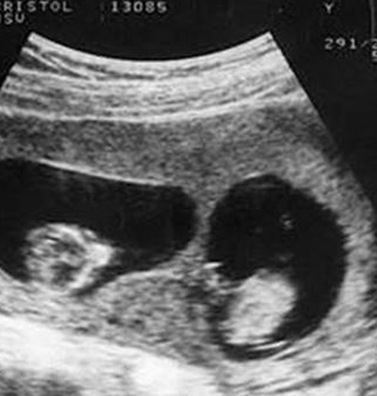

Khi đi siêu âm, Tiểu Mai được bác sĩ thông báo sẽ sinh đôi.

Trong thời kì đầu mang thai, Tiểu Mai, 25 tuổi, người Trung Quốc đi siêu âm và bác sĩ thông báo cô đang mang trong mình thai sinh đôi. Bác sĩ có dặn cô tháng sau tới siêu âm định kỳ nhưng vì bệnh viện ở xa nhà nên Tiểu Mai không tới khám lại nữa.

Trong quá trình mang thai, Tiểu Mai chỉ đi khám 3 lần và sinh con ở tuần thứ 37. Cả gia đình đều chuẩn bị sẵn tâm lý vui mừng để đón 2 đứa trẻ chào đời nhưng sau khi đưa được hai em bé ra ngoài, các bác sĩ nhìn thấy một đôi chân nữa trong bụng Tiểu Mai, họ lập tức đón em bé thứ 3 ra ngoài trong sự ngỡ ngàng.

Không phải 2 mà là 3 đứa trẻ trong bụng Tiểu Mai.

Trên thực tế, Tiểu Mai đã mang thai 3 đứa trẻ, 2 trai 1 gái nhưng khi siêu âm bác sĩ không hề thấy sự hiện diện của đứa trẻ thứ ba nên đã đưa ra kết luận là sinh đôi. Các bác sĩ cũng cho biết, có thể 2 thai nhi kia đã nằm chắn thai nhi thứ 3 nên khi siêu âm không nhìn thấy được. Thật may mắn, đứa bé thứ 3 ra đời rất khỏe mạnh. Vậy là niềm vui của gia đình lại được nhân lên khi mà đáng lẽ họ chỉ có 2 đứa con thì giờ lại xuất hiện thêm một thiên thần nhỏ thứ 3.